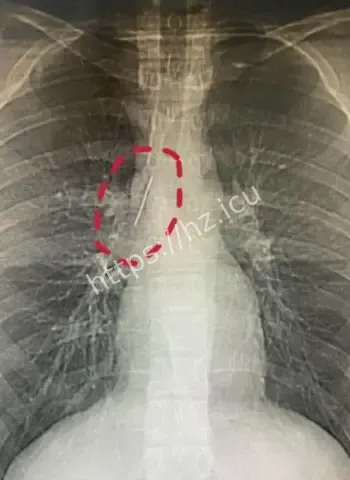

安徽17岁小伙-参军体检发现-或1岁扎入17年无恙-胸腔藏5厘米缝衣针

安徽17岁小伙参军体检意外发现胸腔藏5厘米缝衣针,或1岁时扎入后17年安然无恙,奇闻结合医学解读与生活启示,展现人体惊人适应力,引发广泛热议讨论

安徽17岁小伙胸腔藏5厘米缝衣针17年无恙

哎呦喂这事儿听起来就跟天方夜谭一样,一个安徽的17岁小伙子平时活蹦乱跳的,准备去参军体检,结果医生一照X光片子,眼睛直接瞪圆了,胸腔里居然稳稳当当藏着一根5厘米长的缝衣针。这针估计从小时候就钻进去了,整整17年啊,小伙子吃饭睡觉打球跑步啥都没耽误,身体愣是没闹过一点别扭。换成别人早疼得满地打滚了,他倒好,像没事人似的,这运气简直逆天到让人羡慕嫉妒恨。 想想这17年里,针就这么安静待着,没移位没发炎没刺着要害,估计是身体自动给它裹了一层保护膜,把它当成了自家摆设。

最离谱的是,这针很可能他1岁那会儿不小心扎进去的。小宝宝那时候到处乱爬乱抓,说不定妈妈正缝衣服,他一扑腾就中招了,结果针就这么悄无声息地进了胸腔。17年过去,他从奶娃娃长成大小伙,针却一直老老实实待着,没引起任何不舒服。平时感冒发烧都没多想过胸口,这适应力也太强了吧。 从道理上讲,小孩子身体正长着,组织慢慢把针包得严严实实,像给它建了个小房子隔离起来。没碰着肺叶心脏血管,纯靠运气加体质,简直是活生生的人体奇迹。

参军体检意外发现胸腔惊人异物

参军体检本来是查身体合不合格,谁知道成了挖宝现场。X光一扫,医生估计当时就傻眼了,这么大一根针亮闪闪地躺在胸腔里,小伙子自己都蒙圈了,心想我这身体里藏了啥秘密武器啊。幸好发现及时,要不然以后训练强度一大,万一针跑偏了,后果真不敢想。 这事儿也给大伙提了个醒,重要关口体检千万别马虎,尤其是参军这种人生大事,啥隐藏问题都能揪出来。小伙子估计现在又惊又喜,喜的是没出大事,惊的是自己居然带了17年“隐形伴侣”。

医学解读缝衣针与身体和平共处17年

深入扒一扒,这针为啥能跟身体和平共处这么久呢。首先位置挑得好,没扎着要害器官,胸腔空间大给它留了余地。其次人体有自我保护本能,会分泌纤维组织慢慢把它包裹住,防止感染和移位。小时候扎入,身体还在发育,适应起来更容易。再次可能没带细菌进去,运气成分占大头。 这案例搁医学上都算罕见,值得研究研究,说不定以后处理类似异物就有新办法了。不过小伙子以后肯定得做个小手术取出来,不然总是个小隐患。希望手术顺顺利利,他的参军梦还能接着追,这段经历以后说出去绝对是别人听不够的传奇。